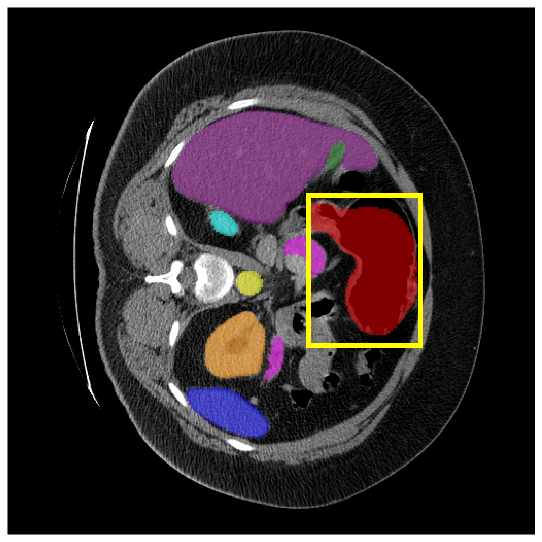

To demonstrate the superiority of our method, additional qualitative comparison results for the ACDC and Synapse datasets are presented in Fig. 6, Fig. 7, respectively. Notably, in the case of GB, the quantitative results in Fig. 7 show relatively lower performance in ‘only ’. However, the visualization results in Fig. 7 reveal instances where the enhanced images identified GB regions that the original images failed to segment, albeit with some boundary over-segmentation. In such scenarios, our proposed method successfully leveraged the information from enhanced images to achieve more accurate GB segmentation. Note that this finding underscores the fact that even when quantitative performance metrics appear lower, the additional information provided by enhanced images can be valuable in the actual segmentation process.